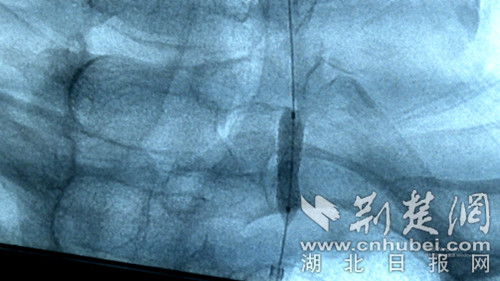

支架植入手術。通訊員供圖

時間就是生命,經過多學科聯合會診,救治團隊決定在患者的腦動脈植入支架,幫助開通患者堵塞的腦血管。3月18日下午,在手術團隊的密切配合下,用時不到一個小時,就完成了全腦血管造影+左側椎動脈球囊擴張+支架植入術。術中患者無明顯不適,生命體征平穩,頭暈癥狀較以前明顯改善。